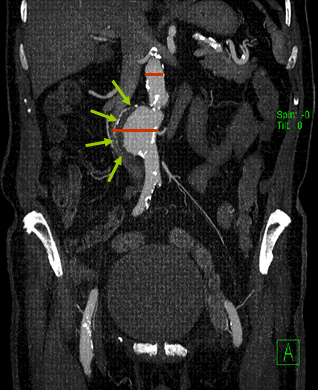

Die Verdachtsdiagnose kann bei schlanken Personen nach Abtasten des Bauchraums gestellt werden. Die Bestätigung der Diagnose wird gewöhnlich mit einem Ultraschallgerät erreicht. Zur weiteren Therapieplanung ist eine Computertomografie in Dünnschichttechnik (Schichtdicke < 1 mm) und selten eine Angiografie (Gefäßdarstellung) erforderlich. Da in der Angiografie nur das durchflossene Gefäß ohne Ablagerungen (wandständiger Thrombus) dargestellt wird, ist das Aneurysma in der Angiografie oft nur angedeutet zu sehen.